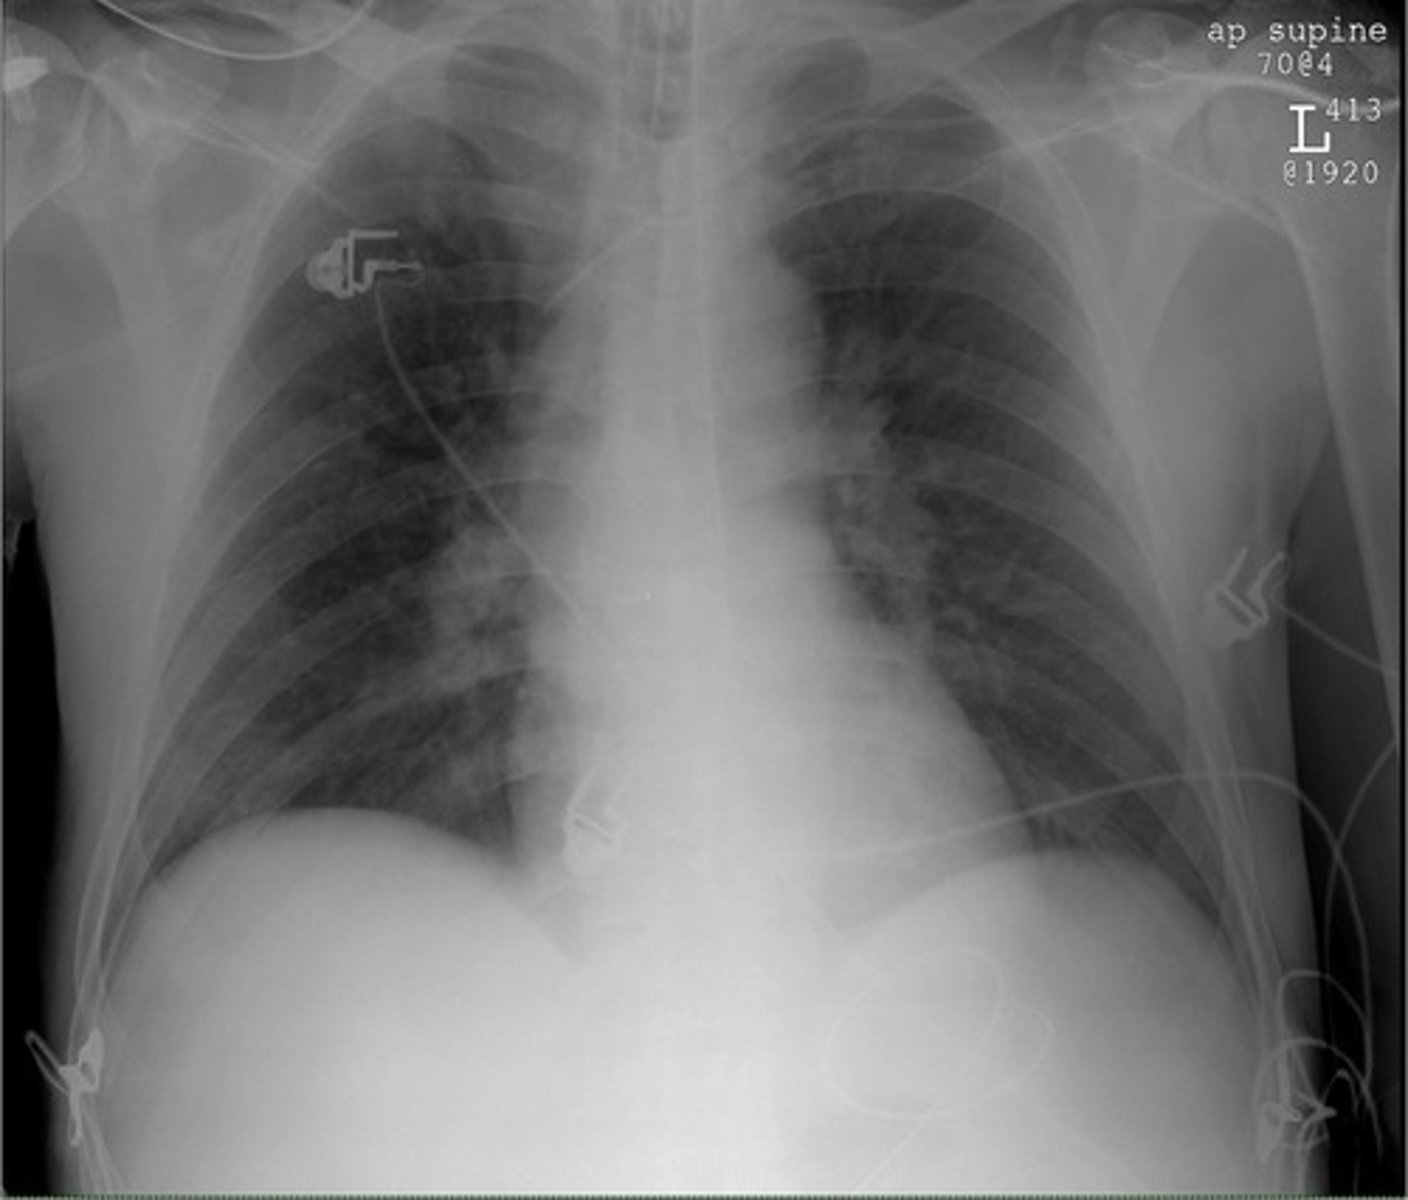

-anteroposterior view

-beam travels front to back

-heart appears large

AP View